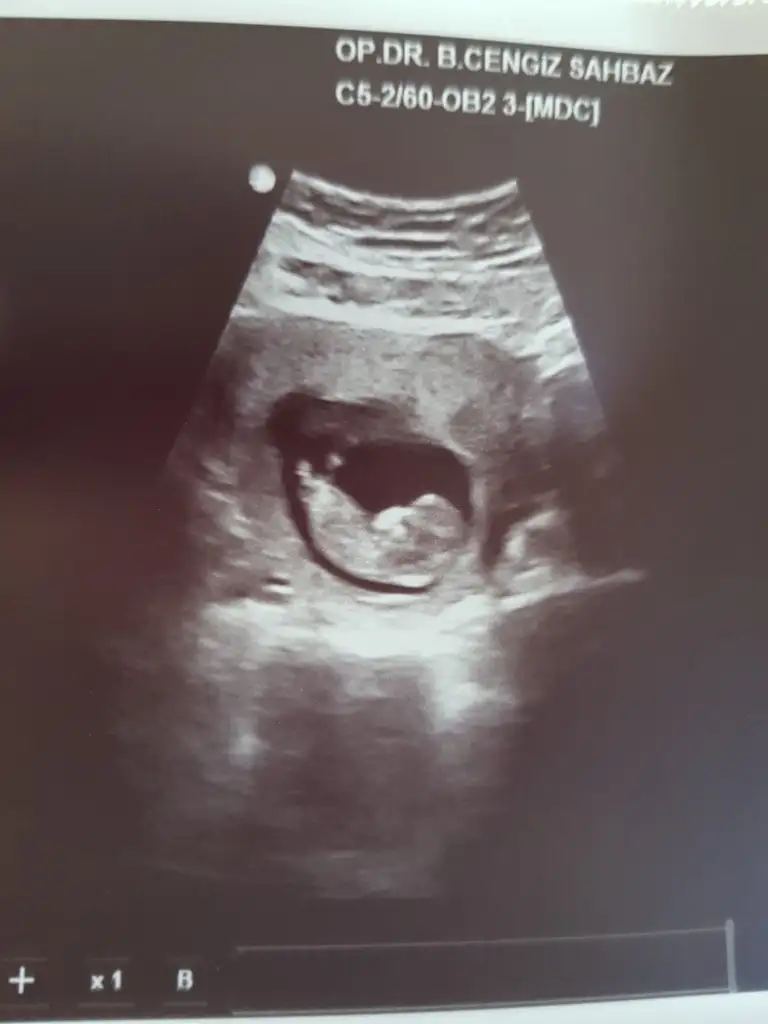

11 hafta iki günlük sizce nedir

• IMG_20190909_144543_2.webp

IMG_20190909_144543_2.webp

10,5 KB · Görüntüleme: 52